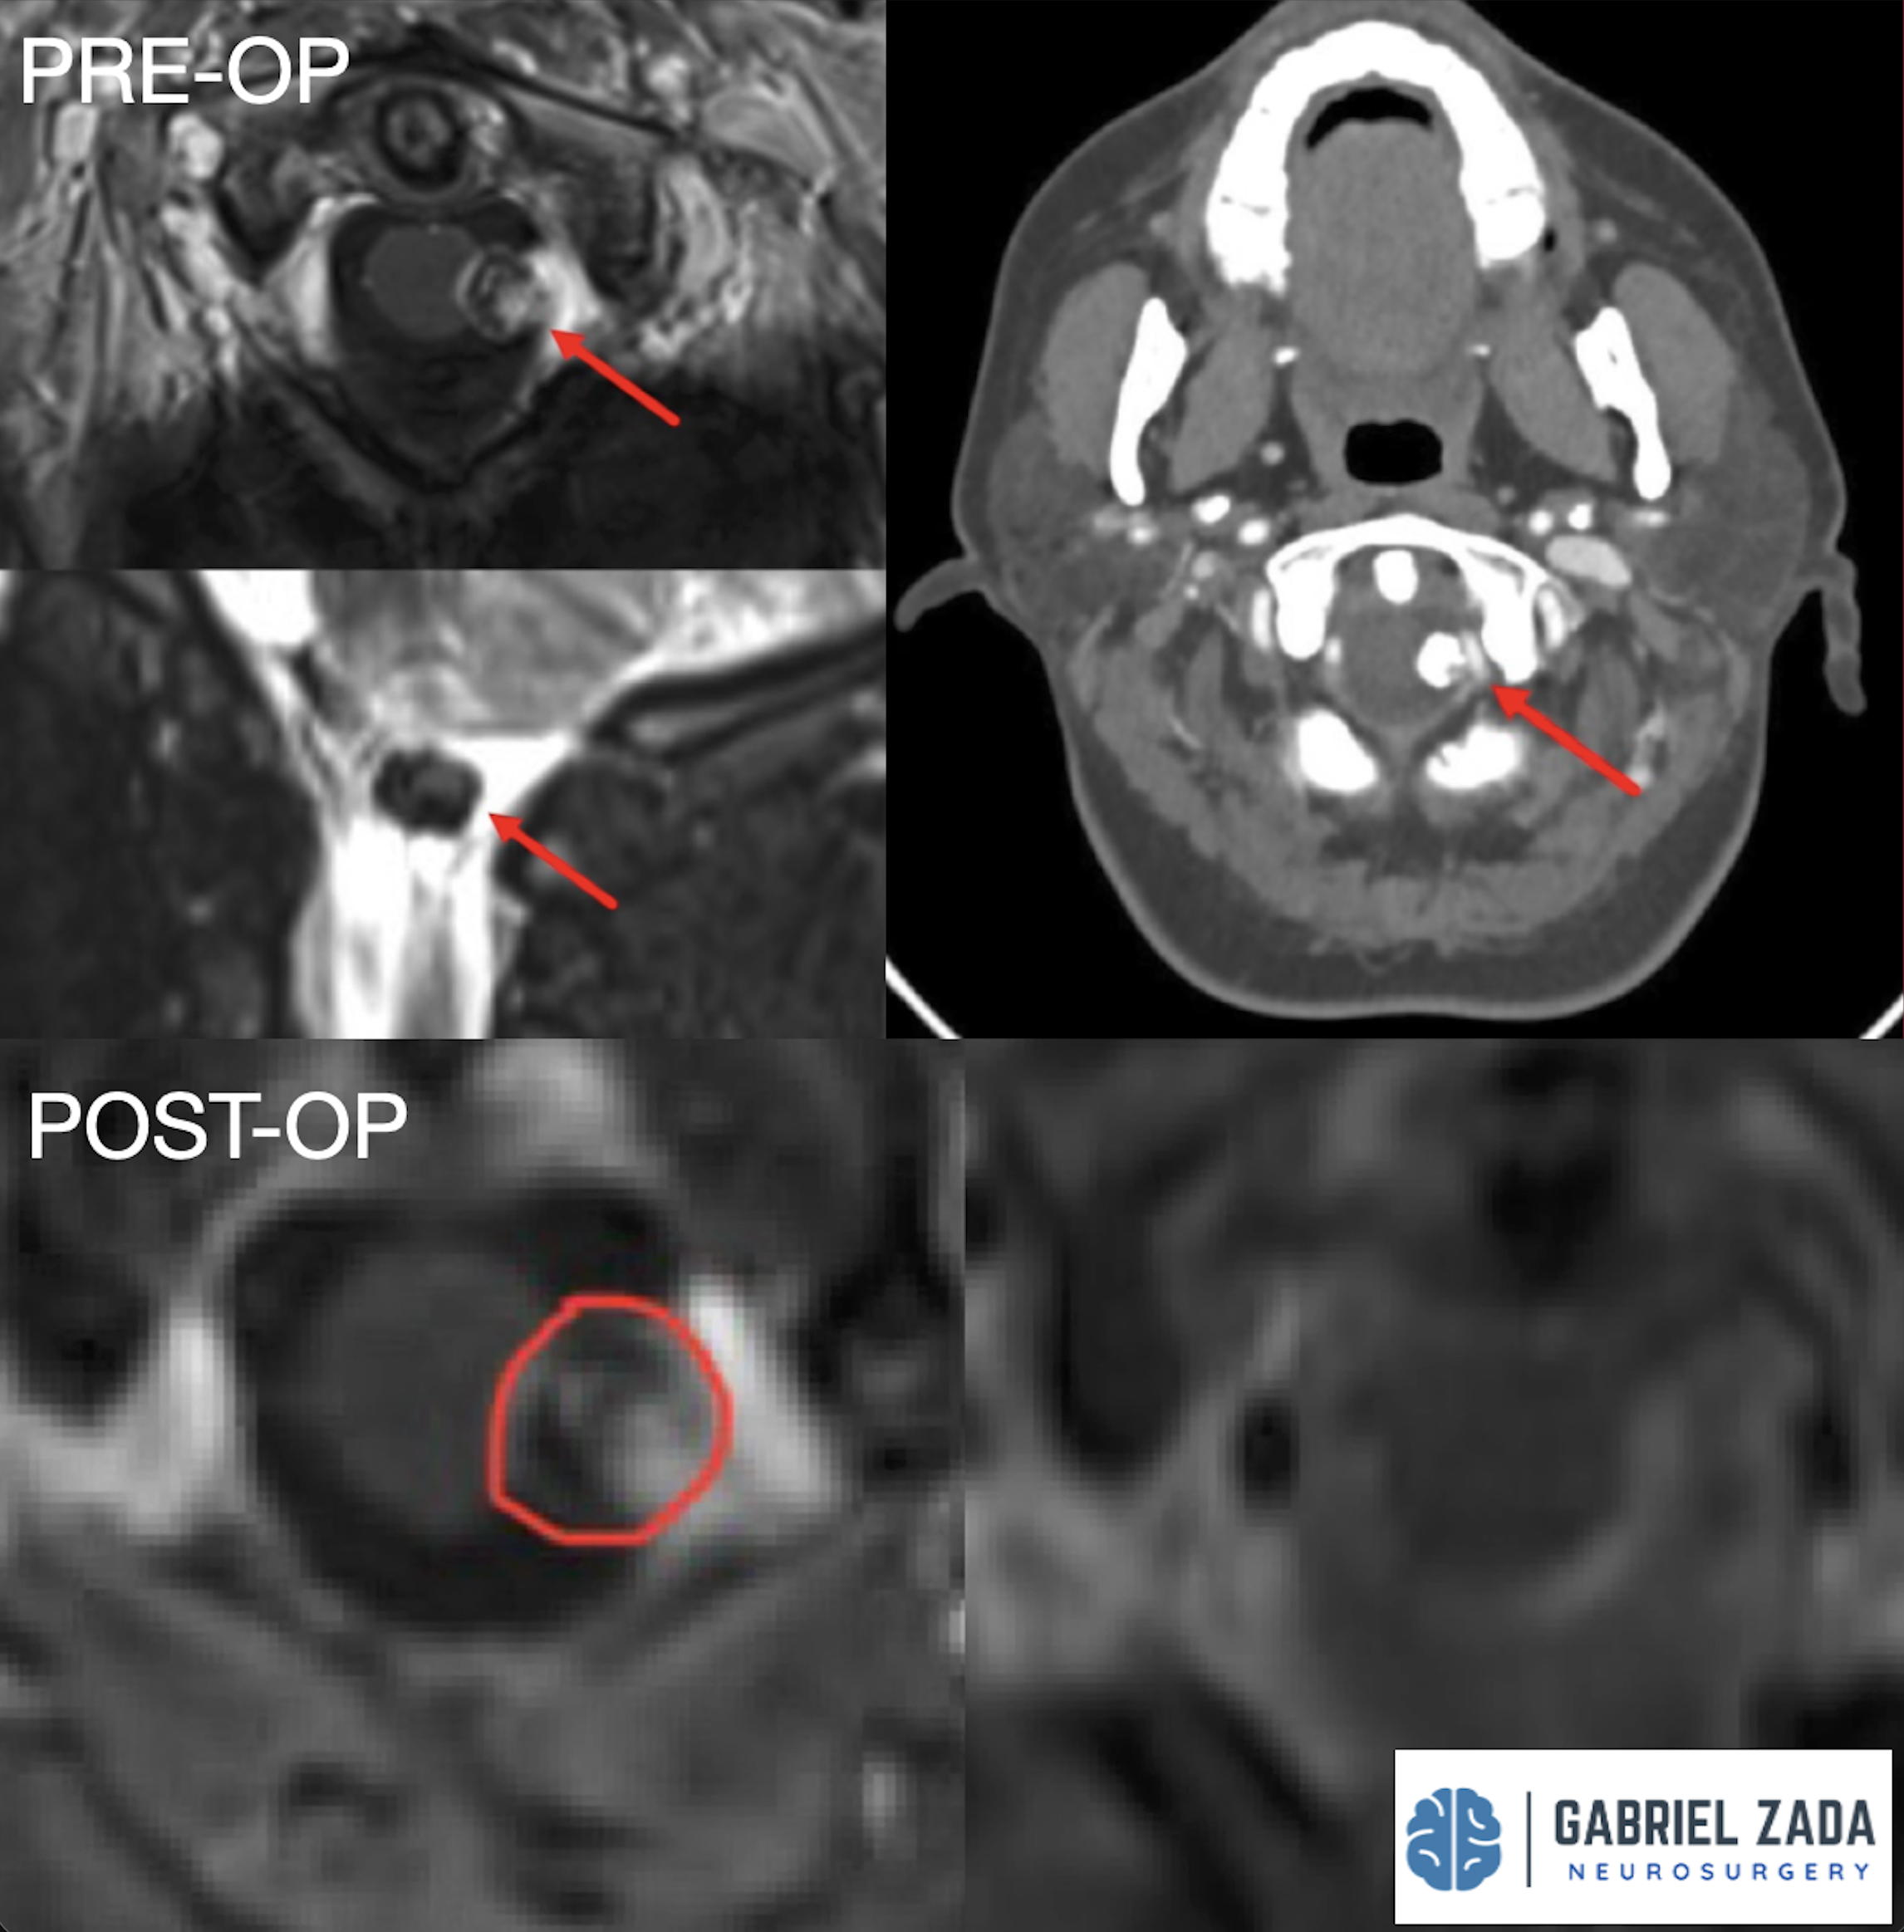

Explore this comprehensive gallery featuring pre‑ and post‑operative imaging of patients with skull‑base tumors treated by Gabriel Zada, MD, MS, FAANS, FACS. These cases highlight Dr. Zada’s expertise in advanced neurosurgical techniques and outcomes.

*Representative cases shown for educational purposes. All images de-identified. Individual results vary.